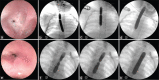

Background: Oesophageal dilatations can be done either by bougies or balloons for differing aetiologies in children. We investigated the efficacy and safety of endoscopic balloon dilatations (EBDs) employed by a single surgeon.

Results: Ninety-seven children underwent 514 EBD with a median EBD of 3 (1-50). The primary diagnoses were oesophageal atresia (OA) in 51 children, corrosive ingestion in 21, peptic strictures in 13, achalasia in 8 and congenital oesophageal stenosis in 4. The balloon size varied between 3 and 30 mm. The EBD was successfully ended in 72 patients and unsuccessful in six patients. Six children are still under EBD and 13 are lost to follow-up. The overall success rate was 92%. The age at the time of first dilatation was the youngest in OA group followed by corrosive strictures. The balloon sizes differed regarding the age of the patients with larger balloons used as the patient age increased. The sizes of the balloons used at the first and the last EBD differed among diagnostic groups. The total number of dilatations or the time interval between the first and the last EBD dilatation did not show a statistically significant difference among groups. The anatomical type of OA or the height of corrosive stricture revealed no significant difference in any of the above parameters. A transmural oesophageal perforation occurred during 2 (0.4%) EBD sessions.

Conclusions: EBD is an effective mean in relieving paediatric oesophageal pathologies with a variety of aetiologies and has a low complication rate.